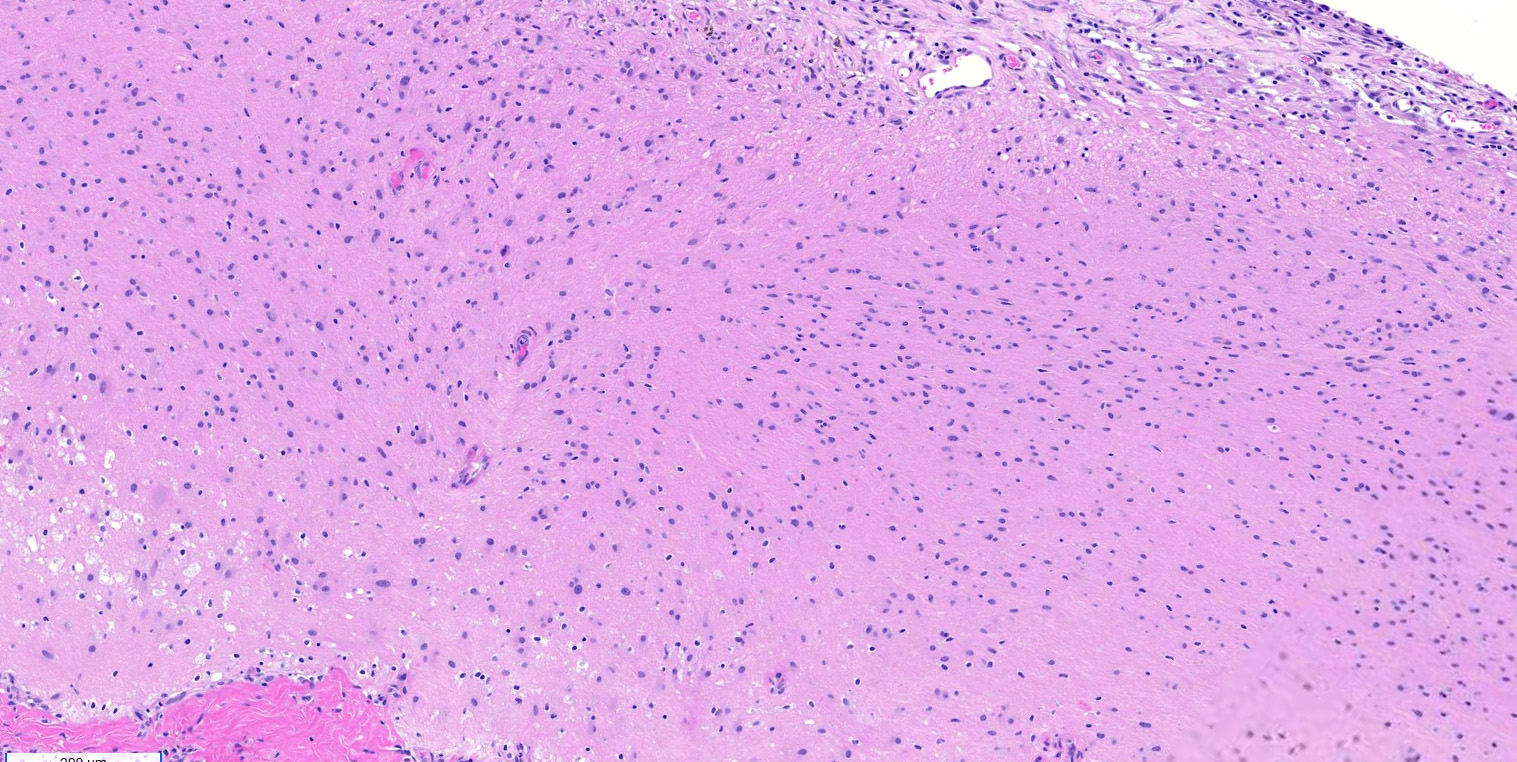

Microscopic (histologic) description

- Mixture of mature, benign tissues

- Ectodermal (most common): squamous epithelium, sebaceous glands, hair follicles, brain tissue

- Microscopic foci of immature neuroepithelium (less than or equal to 4 foci or 21 mm2) does not warrant diagnosis of immature teratoma and will not affect prognosis (Int J Gynecol Pathol 1987;6:203)

- Cases associated with NMDAR encephalitis usually show neuroglial tissue associated with lymphoid aggregates with germinal centers, low number of mature neurons and a hypercellular astrocyte population (Am J Surg Pathol 2019;43:949)

Microscopic (histologic) images